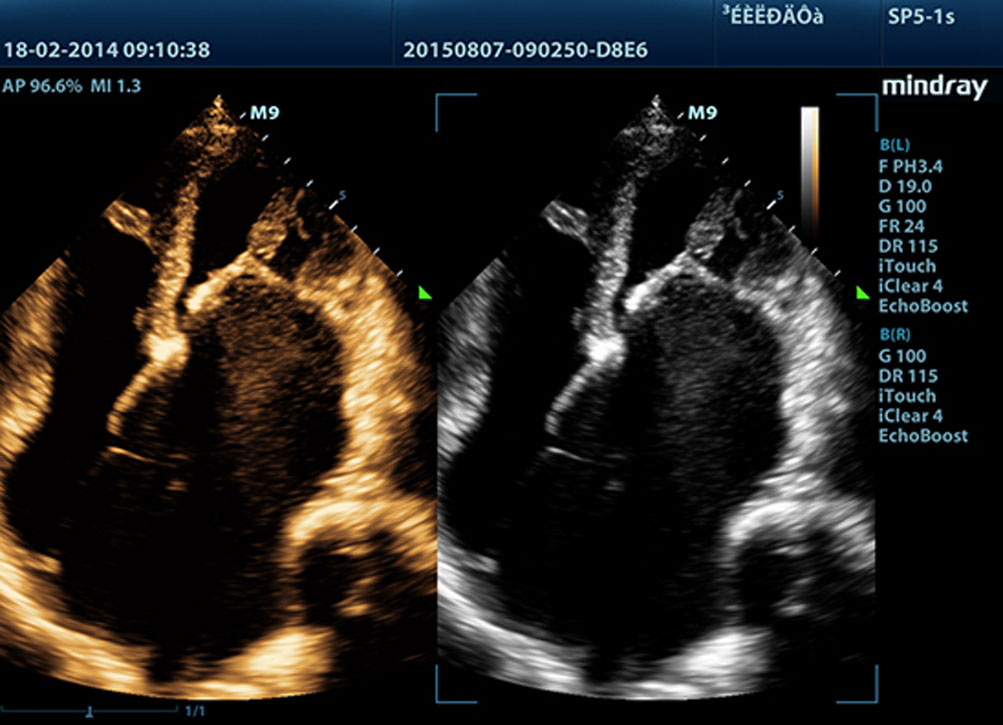

Echo Boost?

?evredeki parazit gĂŒrĂŒltĂŒleri bast?r?rken gĂŒ?sĂŒz eko sinyallerini art?rmak i?in ba??ms?z sinyalden-gĂŒrĂŒltĂŒye bilgisini kullanmak ĂŒzere tasarlanm?? ak?ll? eko tespit ?zelli?i ile Mindray'in benzersiz uyarlanabilir sinyal i?leme teknolojisi, daha dengeli g?rĂŒntĂŒ parlakl??? ve miyokard doku katmanlar?n?n daha iyi g?rĂŒntĂŒlenmesini sa?lar.